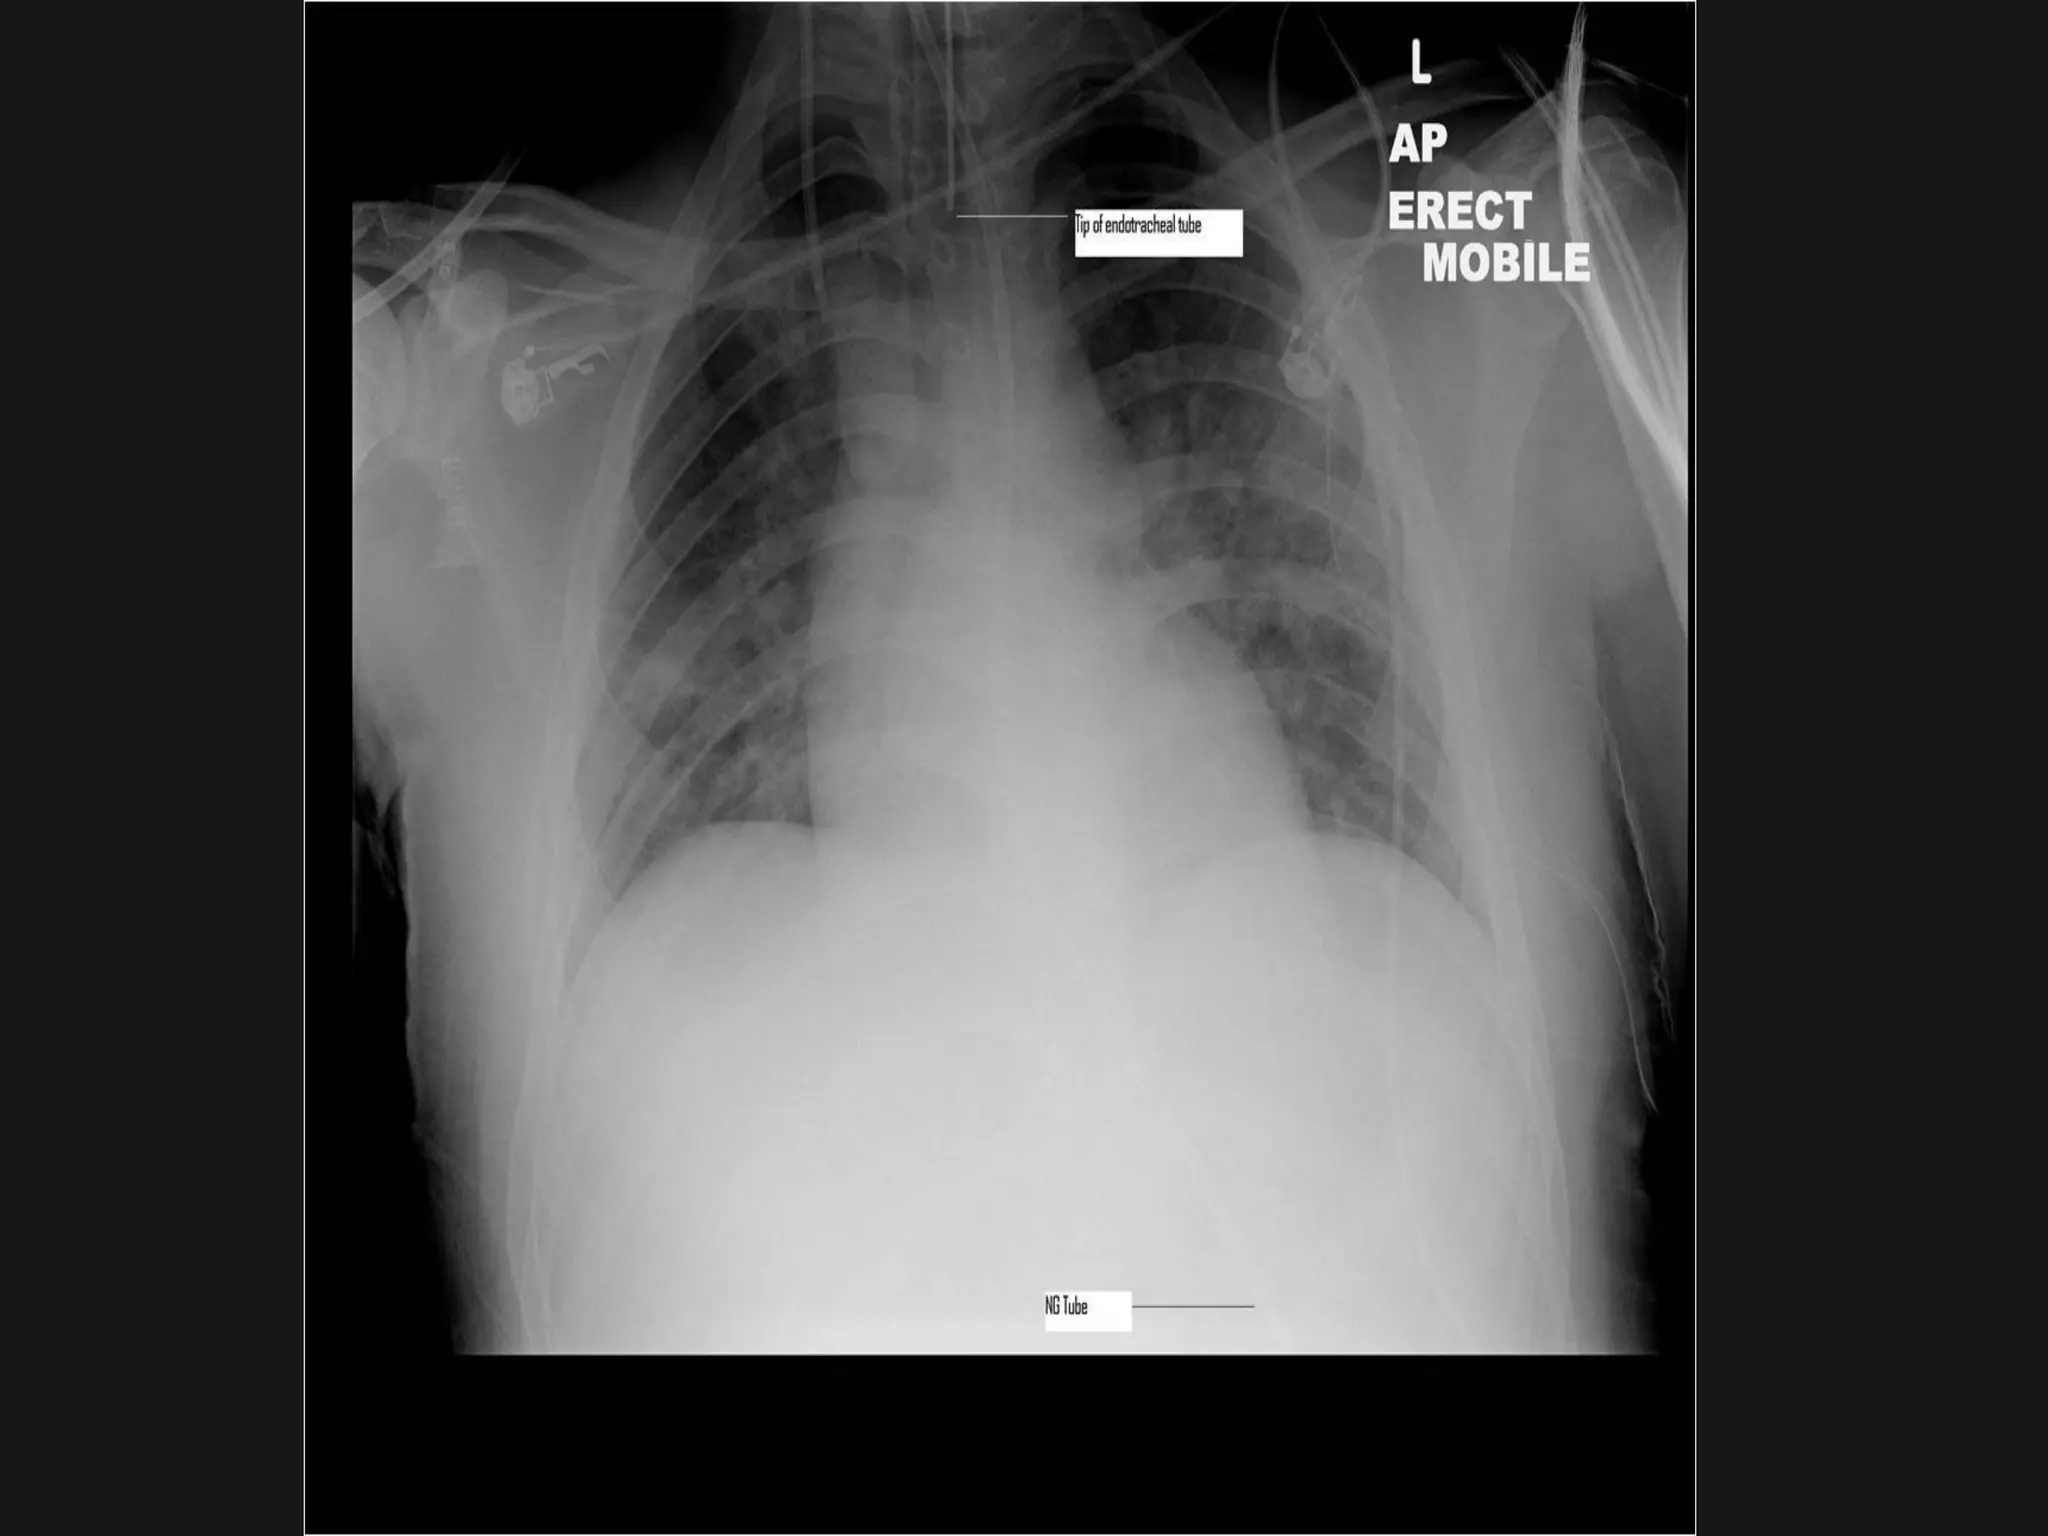

ICU nutritionICU nutrition

 Used to be everything mixed up and givenUsed to be everything mixed up and given

via NG tubevia NG tube

Naso-gastric FeedingNaso-gastric Feeding

 Risk of aspiration in ICU: HOB 30 degreesRisk of aspiration in ICU: HOB 30 degrees

 Absence of bowel sounds/flatus not aAbsence of bowel sounds/flatus not a

marker for withholding feedmarker for withholding feed

 Rotine practise of GRV measuring isRotine practise of GRV measuring is

discourageddiscouraged

 Prolonged stopping for diagnosticProlonged stopping for diagnostic

purposes is not recommendedpurposes is not recommended

 PEG/gastrostomy feeding for long-termPEG/gastrostomy feeding for long-term